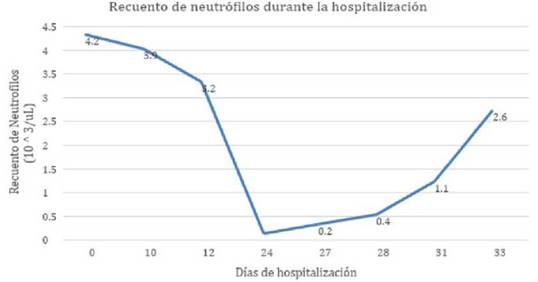

Tabla 1: Recuento de laboratorios durante la hospitalización. Se observa neutropenia absoluta al día 24 de tratamiento.

Durante su hospitalización se realiza Tomografía Axial Computarizada (TAC) de cráneo donde se reporta ocupación masteoidea derecha asociado a cambios líticos que condicionan pérdida de tabiques de celdillas mastoideas y comunicación con estructuras intracraneales (Ver figura 1). Se decidió iniciar tratamiento intravenoso a base de vancomicina a 60 mg/kg/día y piperacilina - tazobactam a 60 mg/kg cada 6 horas hasta su resolución quirúrgica, sin embargo, presentó pico febril aislado al día 24 de tratamiento, sin otras manifestaciones clínicas agregadas. Se realizó biometría hemática de control posterior al evento febril, donde se identificó leucopenia, con un recuento de neutrófilos de 0 x 10^3/uL, clasificándola como una neutropenia profunda, además se encontró una disminución del recuento plaquetario sin catalogarse como trombocitopenia. Dada su larga estancia intrahospitalaria sin otros antecedentes hematológicos se sospechó de neutropenia secundaria a fármacos, por lo que se utilizó la escala de Naranjo para identificar la posible causalidad entre los fármacos utilizados en el paciente, obteniendo una puntuación de 7 para vancomicina (probable)17. Para descartar la etiología autoinmunitaria se realizaron pruebas para anticuerpos anti-citoplasma de neutrófilos (ANCA) resultando negativos. El día 24 del uso de vancomicina se suspendió tratamiento y se continuó con un fármaco derivado de lincomicina (clindamicina). A las 72 horas del retiro del fármaco se realizó un control de laboratorios observando un incremento en el recuento de neutrófilos, con una recuperación total al día 9 de la suspensión del fármaco (Ver figura II). Es valorado por el servicio de otorrinolaringología (ORL) pediátrica, se decidió realizar una mastoidectomía radical amplia derecha con timpanoplastía, la cual se realizó sin complicaciones. El paciente presentó evolución favorable sin datos de parálisis facial con recuperación gradual de la hipoacusia. Se egresó con cita a la consulta externa de ORL donde actualmente se reporta sin secuelas.

El primer caso reportado en pacientes pediátricos se realizó en 1994 por Y. Todd y colaboradores, en un preescolar de 2 años con sospecha de endocarditis secundaria a un defecto del tabique interventricular, después de 18 días de tratamiento con vancomicina con un recuento mínimo de neutrófilos de 990 x 10^3/uL18, en comparación, nuestro paciente presentó una afección más marcada, documentándose una neutropenia absoluta de 0x10^3/uL, sin otras manifestaciones clínicas. Dintel y colaboradores reportaron afección a otras líneas celulares en un adulto, con una tríada inusual que desarrolló leucopenia, trombocitopenia y eosinofilia6, sin embargo nuestro caso mostró únicamente afección al recuento absoluto de neutrófilos, conservando niveles normales de plaquetas y eosinófilos. De la misma forma en la que se describe en pacientes adultos, la neutropenia en nuestro paciente apareció después de los 14 días del tratamiento con vancomicina, sin requerir evaluación de los niveles séricos del fármaco, dada la escasa relación con la aparición del cuadro, como se describe en la literatura12,19.

Una vez determinada la afección hematológica se realizó la escala de Naranjo para deteriminar la causalidad de los fármacos utilizados en nuestro paciente, encontrando una escala de 7 la cual se determina como probable17. Al suspender el fármaco y para continuar con la cobertura para microorganismos meticilino-resistentes, se utilizó clindamicina, respaldando las directrices de la Sociedad de Enfermedades Infecciosas de América21. Estudios en pacientes adultos han reportado una recurrencia rápida y más intensa con la reexposición a vancomicina o fármacos del grupo de los glucopéptidos. Hsiao y colaboradores reportaron el caso en un adulto que presentó una reinducción a la neutropenia al cambiar el tratamiento por teicoplanina, producto de una posible reacción cruzada entre los 2 fármacos19, éstas son consideraciones que se deben de tomar en cuenta al establecer la conducta terapéutica20-21. Finalmente algunos estudios informan el uso de Factor estimulador de colonias de granulocitos (G-CSF) para favorecer el incremento en el recuento de neutrófilos, sin embargo en nuestro paciente la recuperación hematológica se suscitó en las primeras 72 hrs de la suspensión de la vancomicina, tiempo esperado según lo reportado en la literatura, sin necesidad de terapia adyuvante19-21.